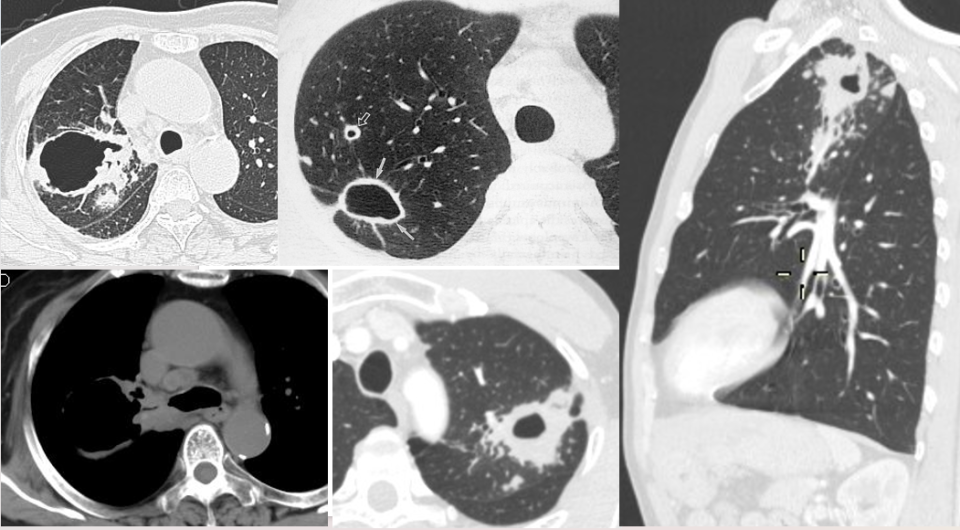

刚才有两个对比的病例中,有个患者同样是经过抗感染,2个月后肿块没有

图片尺寸960x437